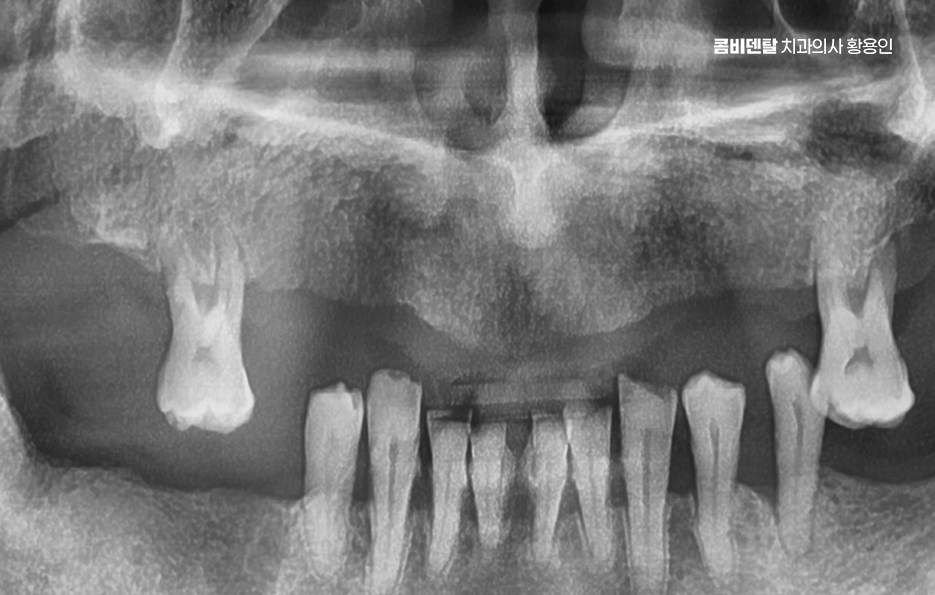

윗니가 하나둘 빠지기 시작했을 때까지만 해도 이렇게까지 될 줄은 몰랐어요. 처음엔 단순히 오래된 충치가 더 이상 버티지 못해서 빠졌다고 생각했어요 그런데 어느 순간부터 그 ‘하나둘’이 점점 늘어나더니, 이제는 위쪽 치아 대부분이 사라져 버렸고, 윗니가 비어 있는 모습이 너무 낯설게 느껴졌어요. 그때는 몰랐어요. 치아는 하나 빠지면 주변까지 영향을 받고, 잇몸뼈는 생각보다 빨리 무너질 수 있다는 것을 말이에요 임시 틀니를 잠시 사용하고 있는데, 그 불편함은 말로 다 설명하기 어려울 정도였어요

윗니 전체를 임플란트로 치료해야 하는 상황이 생겼다는 건 단순히 몇 개 치아를 잃은 게 아니라, 치아 기능 전체가 무너졌다는 의미이며 이런 경우에는 단순히 개별 치아 하나하나를 심는 방식으로 접근하면 비용도 고가이고 비효율적이며 구조적으로도 안정성이 떨어질 수 있기 때문에 처음부터 전체적인 구강 구조를 고려한 통합적인 치료 계획이 필요할 수 있어요

특히 윗니는 웃을 때 많이 보이는 부위이고 심미적으로 얼굴 인상을 결정짓는 중요한 부분이기 때문에, 단순히 저작 기능만 회복하는 데 그치지 않고 얼굴형, 잇몸선, 말할 때 입술의 움직임, 교합의 균형까지 고려한 섬세한 설계가 필요해야 하고 이 모든 걸 고려해서 치료하는 게 바로 윗니 전체 임플란트 치료라고 할 수 있어요

보통 윗니 전체 임플란트를 계획할 때 먼저 해야 하는 건 CT 촬영을 통한 잇몸 뼈 상태 진단으로 윗니는 아래보다 뼈가 더 얇고, 특히 어금니 쪽에는 상악동이라는 빈 공간이 있기 때문에, 임플란트를 심을 수 있는 잇몸 뼈의 양이 부족한 경우가 많다보니 이런 경우에는 단순히 임플란트를 심을 수 없기 때문에 상악동 거상술이라는 수술이 필요하게 되는 경우도 있는데요